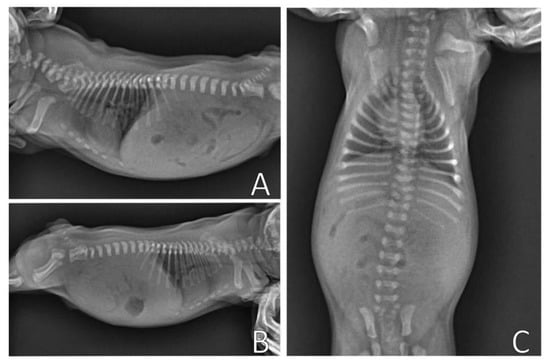

The evaluation of pectus excavatum can be performed by measuring the frontosagittal and vertebral indices (Figure 1) on chest X-rays [15,16,19]. Table 1 shows the normal thoracic indices in dogs of nonbrachycephalic breeds, brachycephalic breeds and cats. Based on these indices, pectus excavatum can be classified as mild, moderate or severe [15,16,19] (Table 2). Figure 2 shows radiographs of neonatal puppies of brachycephalic breeds with normal thoraxes and with different degrees of pectus excavatum.

Figure 2.

Chest X-rays of neonatal puppies of brachycephalic breeds. (A) Chest without alterations, indices—frontosagittal: 1.14 cm; vertebral: 13.4 cm. (B) Pectus excavatum of mild degree (arrow), indices—frontosagittal: 2 cm; vertebral: 11.25 cm. (C) Pectus excavatum of moderate degree (arrow), indices—frontosagittal: 3 cm; vertebral: 6 cm. (D) Severe pectus excavatum (arrow), indices—frontosagittal: 3.14 cm; vertebral: 5.8 cm.